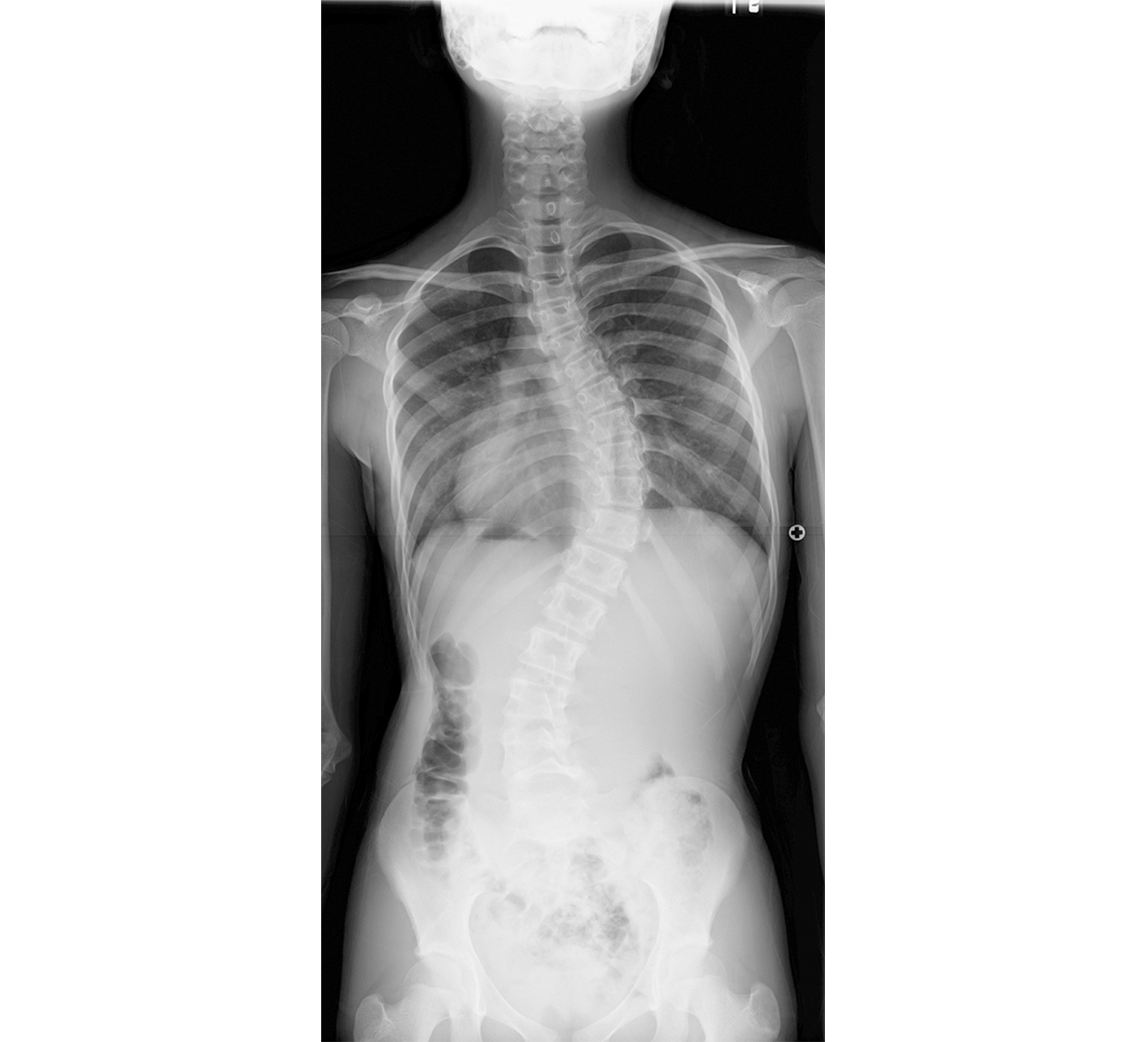

特発性側弯症(腰椎カーブ)の立位全脊柱X線正面像

T11-L3にCobb角50°の腰椎カーブを認めた(a)。前方矯正固定術により、Cobb角は0°に矯正された(b)。後方固定に比較し多くは固定範囲を少なくすることができる(可動椎間を多く残すことができる)。